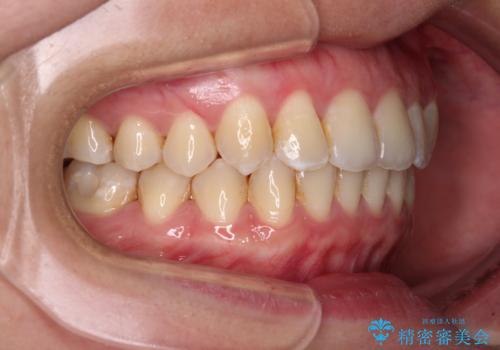

上顎の拡大に伴い反対咬合があっという間に改善されました。

元々の歯列不整は軽微であったため、僅か1年の期間で治療を終えることができました。